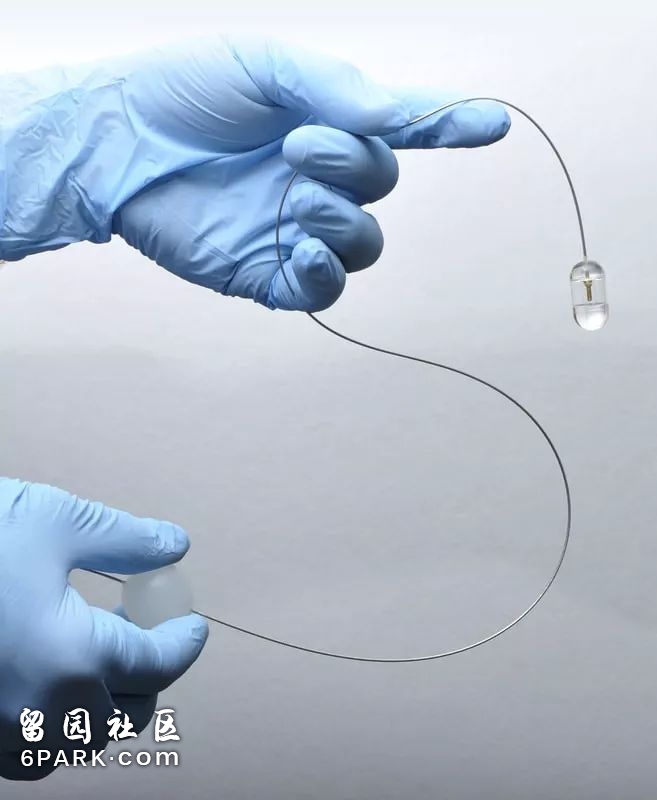

▲Guillermo Tearney教授研发的显微胶囊 | Tearney实验室官网

麻省总医院的病理学家和工程师Guillermo Tearney教授研发出一种可吞咽的小型设备,用于诊断胃肠道疾病。患者无需麻醉,在吞下胶囊状的显微内镜后,由医务人员牵引胶囊上连接的导线,短短几分钟就可以捕捉到整个消化道的三维显微图像,比内窥镜的应用更简单。并且,胶囊被导线拉出后,经过消毒可以重复使用。

这种小型探测仪可以帮助医生和科学家检测和研究消化道疾病。目前,已在成人患者中用于筛查巴雷特食管症——食管癌的前兆之一。Tearney教授的研究团队还在继续研发更小的版本,以便给吞不下胶囊的婴儿使用。